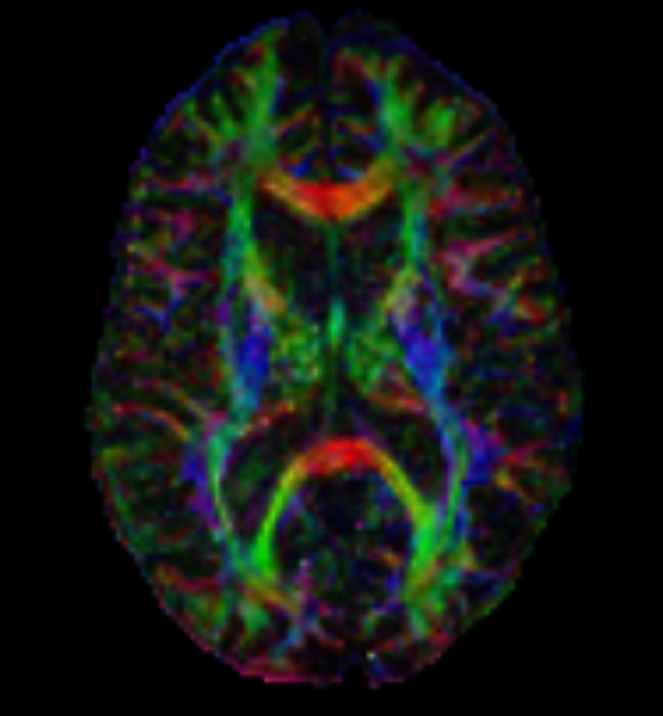

Diffusion Imaging (DWI, DTI, DSI, etc.)

Examples of DWI on the left, DTI color maps on the right, DTI and DKI below.

Diffusion describes the constant random motion that all molecules undergo because of their intrinsic thermal energy. Clinical diffusion weighted imaging (DWI) studies the molecular motion of water, probing its mobility on the cellular scale. The diffusion coefficient, measured in mm 2 /sec, relates the average motion, in a mean-squared sense, to the observation time, with higher values of this coefficient indicating more mobile water molecules. The apparent diffusion coefficient (ADC) characterizes water mobility observed in the clinical setting, reflecting the limitation that, in vivo, pure diffusion cannot be easily separated from other sources of water mobility, such as active transport, changes in membrane permeability, and pressure gradients.

Advances in Diffusion Imaging have yielded opportunities to evaluate and visualize not only ischemic injury and stroke, but also nerve fiber tracts. Several techniques that are being used include Diffusion Tensor Imaging (DTI), Diffusion Spectrum Imaging (DSI), and Diffusion Kurtosis Imaging (DKI).